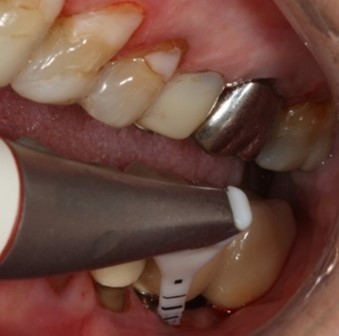

Au stade de « péri-implantite » il s’agit d’une atteinte inflammatoire des tissus mous entourant un implant. Le diagnostic clinique comprend un saignement au sondage, avec une suppuration quasi systématique, et une profondeur de poche péri-implantaire supérieure ou égale à 5 mm. Radiographiquement, un aspect radioclair de déminéralisation osseuse marginale supérieure ou égale à 2 mm entoure une partie plus ou moins étendue du corps de l’implant (fig 1 et 2).

Figure 1: suppuration au sondage d’une molaire atteinte de péri-implantite

Figure 7: aéro polissage de la surface implantaire à l’aide d’une tête fine (Prophyflex Kavo), après élimination du tissu de granulation